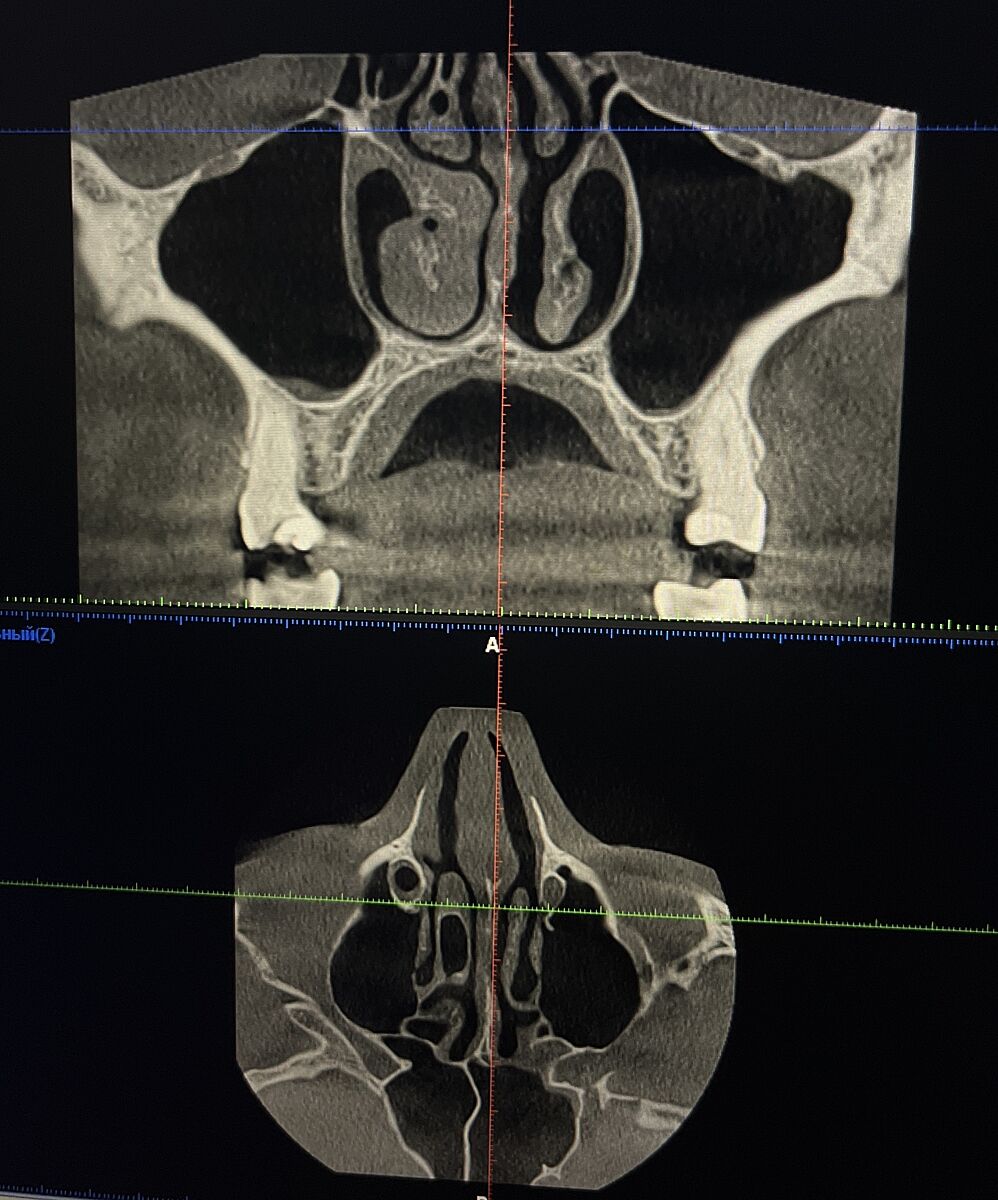

Есть ли что-то критичное на кт?

Сделала кт зубов, но он захватил и нос, решила посмотреть и увидела вроде как киста. Есть кто-нибудь кто разбирается?

К лору - искривление носовой перегородки и вследствие этого гипертрофия нижней носовой раковины. Дышите носом нормально? Даже в лежачем положении?

Кист не вижу. Реактивное утолщение слизистой в гайморовой пазухе, возможно от корня зуба - там стоматолог глянет.